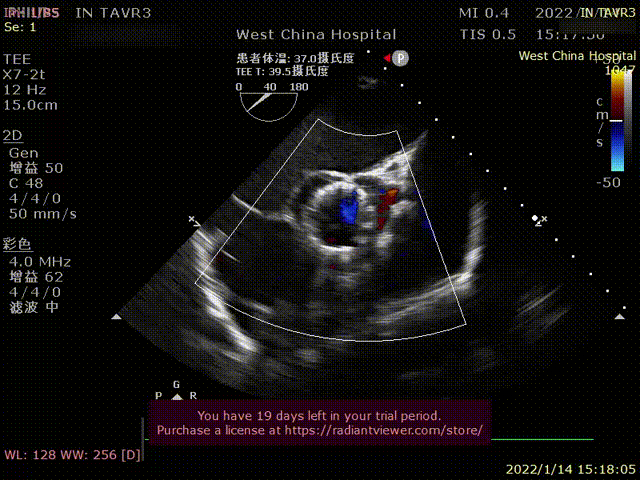

患者为70岁女性,因“心悸、胸闷16余年,反复1年,加重1天 “主诉入院。术前超声提示左心增大,左室为著,LVDD 71mm,LVEF 41%,主动脉瓣中重度反流。术后即刻主动脉瓣大量反流消失,LVDD 62mm,左心较术前明显缩小。

术前超声影像

术后超声1

术后超声2